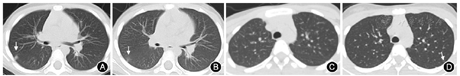

15例患儿治疗3~5 d后复查病毒核酸、外周血血常规及胸部CT:白细胞计数偏低3例,白细胞计数正常12例。病毒核酸转阴性者6例,其中2例患儿胸部CT炎症较前吸收减少(图2),3例患儿肺部仍未见病灶,1例患儿胸部CT炎症无明显变化;病毒核酸仍阳性者9例,其中6例患儿胸部CT炎症表现较前无明显变化,3例患儿复查胸部CT新见炎症表现,均表现为小结节磨玻璃影且均局限于单个叶段(表1)。

例4 女,10岁,无发热,因接触确诊患者后行病毒核酸筛查阳性入院,入院治疗4 d复查病毒核酸仍阳性,复查CT新见左肺上叶小结节磨玻璃影(图2);例6女,6岁,无发热,因接触确诊患者后行病毒核酸筛查阳性入院,入院治疗5 d复查病毒核酸仍阳性,CT新见右肺中叶小结节磨玻璃影;例15女,4岁,无发热,因接触确诊患者后行病毒核酸筛查阳性入院,入院治疗5 d复查病毒核酸仍阳性,CT新见左肺下叶小结节磨玻璃影。